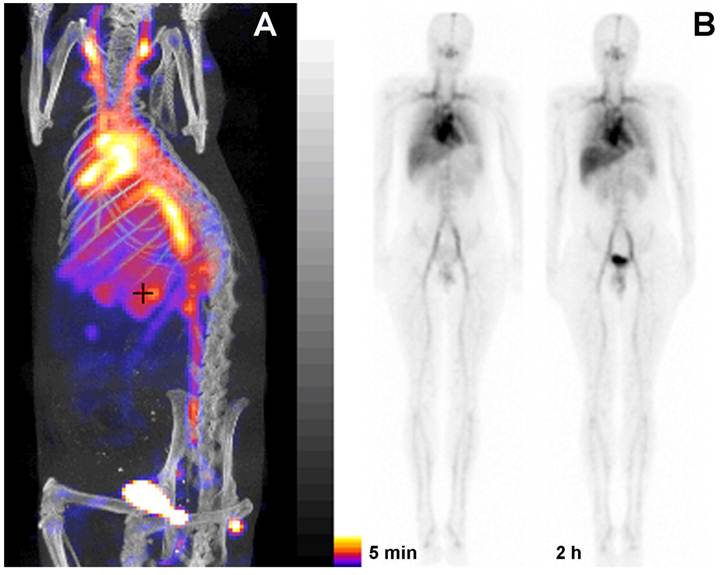

Figure 5

PGC as a blood pool imaging agent. A- a fusion SPECT/CT image of a rat 30 min after the injection of 99mTc-labeled PGC (2 mg PGC-DTPA/kg, 1 mCi 99mTc/rat). The image was obtained using NanoSPECT/CT (Bioscan Inc.); B- an image obtained in a healthy volunteer during Phase I clinical trials. Serial anterior whole-body images are shown taken immediately (30 min) and 2 h after the injection of 25 µg PGC-[99mTc]DTPA/kg (total dose - 20 mCi 99mTc). Note the distribution in the blood pool and low uptake in the lung, spleen and liver. Adapted from [38].

We have also developed PGC-DTPA for blood pool imaging in nuclear medicine applications. We hypothesized that the availability of a long-circulating synthetic molecule that could be easily labeled with gamma-emitting isotopes would obviate the need to use human blood components as carriers for isotopes and therefore would be a substantial improvement in patients' and operators' safety. Our major expectation was that PGC-DTPA could be formulated into a kit form which needs only the addition of pertechnetate-99m solution to obtain a [99mTc]-labeled injection-ready preparation for imaging left ventricular ejection fraction in oncology patients undergoing potentially cardiotoxic treatments [37].

To obtain a labeling kit, we combined PGC-DTPA with a buffering solution in the presence of Sn(II) to enable reductive conversion of pertechnetate to a Tc oxocomplex [37]. After testing the kit in vitro and in three animal species [37] (representative SPECT/CT image in rats Fig. 5A) we tested PGC-DTPA[99mTc] in a phase I clinical trail that showed promising results. Twenty mCi (70 MBq) of the compound were injected I.V. and serial anterior and posterior whole body images were collected immediately and after a delay [38] (Fig. 5B). The compound showed the expected distribution and the heart and major blood vessels were clearly distinguishable up to 24 h post injection. The blood half life of the compound was 20.6 ± 2.3 hr. In four of the volunteers 22.1% ± 2.5% of the compound had been excreted through the kidneys 24 hr after iv administration, while the other two volunteers showed a greater distribution of the agent to the liver and spleen presumably due to DTPA labeling instability and not due to immunogenicity. A combination of the PGC long blood half-life with the advantages of a simple labeling protocol make this synthetic copolymer kit a potential substitute for blood products in blood pool imaging under the conditions when other blood pool imaging modalities fail to produce adequate results.